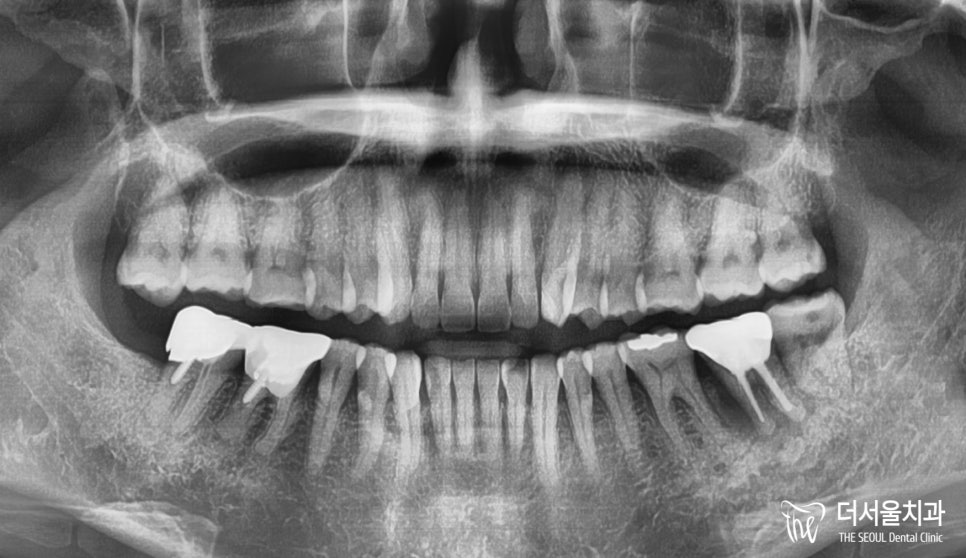

첫 내원때 찍은 X-Ray인데,

여러분들께서는 어떤 곳이 문제가 있는지

찾을 수 있으실까요?

조금만 자세히 살펴봤을때,

그 답을 찾을 수 있습니다.

혹시 찾으셨을까요?

그럼 답을 한 번 확인을 해보겠습니다.

정답은 37번 어금니였습니다.

잇몸 부근을 보셨을때,

시커멓게 변해있는 것을 볼 수 있죠?

이미 염증이 진행된 것으로

다른 치아에 영향을 끼치려 하기 전에

발치 후 염증을 제거해줘야 되었습니다.

그런데 이미 옆에 있는 36번 어금니는

부러져있는 상태였습니다.

아예 되살릴 수 없을 정도였기에

발치 후 즉시 픽스처를 심어드렸는데요.

이는 염증이 없었기 때문

판교 치과 에서

즉시 심을 수 있었던 것이였습니다.